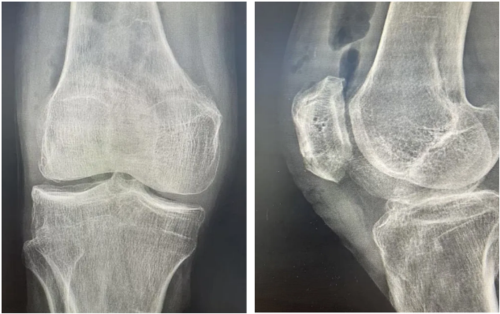

不久前,73岁的张大爷(化名)因外伤导致膝盖剧痛,无法站立行走,前来我院就诊。骨科团队为其完善术前影像学检查后,明确诊断为髌骨下极粉碎性骨折,且骨折块分离移位明显。“当时心头慌得很,听说这种骨折要开刀放钢钉,后面还得再挨一刀取出来,我这么大年纪害怕扛不起啊!”张大爷回忆起当初的担忧仍心有余悸。

术前影像学检查显示髌骨下极粉碎性骨折、分离移位明显